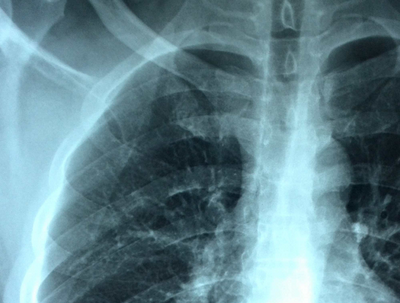

肺气肿的病因其实现在在医学界还没有形成特别详尽完善的机制,但是它同我们平时的生活、环境都是息息相关的。一般来说在空气质量差的环境中,进入呼吸道的空气堵塞在肺部无法释放出来,长期积压之后肺部支气管和毛细血管发生破裂,于是肺部的循环无法正常进行,因此,人体的机能不能及时被提供,尤其是呼吸就会发生困难。